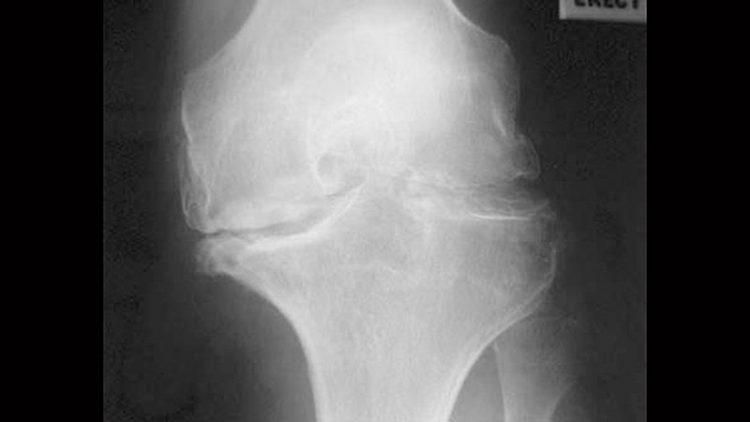

In randomized clinical trials, middle-aged and older patients who underwent arthroscopic partial meniscectomy fared no better than patients who received sham surgery or who simply performed exercises to improve their knee symptoms.

Older patients typically have degenerative meniscal tears, often in combination with other degenerative changes, such as knee osteoarthritis, the researchers point out.

Younger patients are more likely to experience a traumatic meniscal tear, such as through a sports injury, in an otherwise normal joint. As a result, symptoms are more likely to originate from the meniscal tear, resulting in a loss of meniscus function, the researchers say.